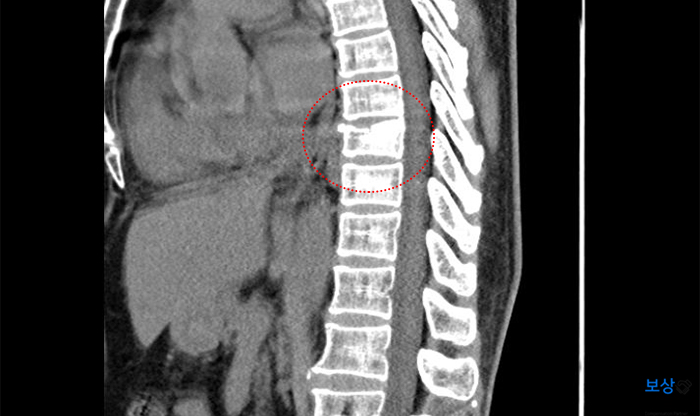

P 님은 자택으로 올라가시던 중 계단에서 넘어져 허리 쪽에 충격을 받으셨습니다. 병원에 내원하여 정밀 검사 결과 **"흉추 9번 급성 압박골절" **진단을 받으셨는데요.

image

다행히 척수 침범이나 추가적인 증상이 우려되지 않아서 수술은 하지 않으셨는데요. TLSO 척추 보조기 착용하는 보존적 치료를 3개월간 받게 되셨습니다.